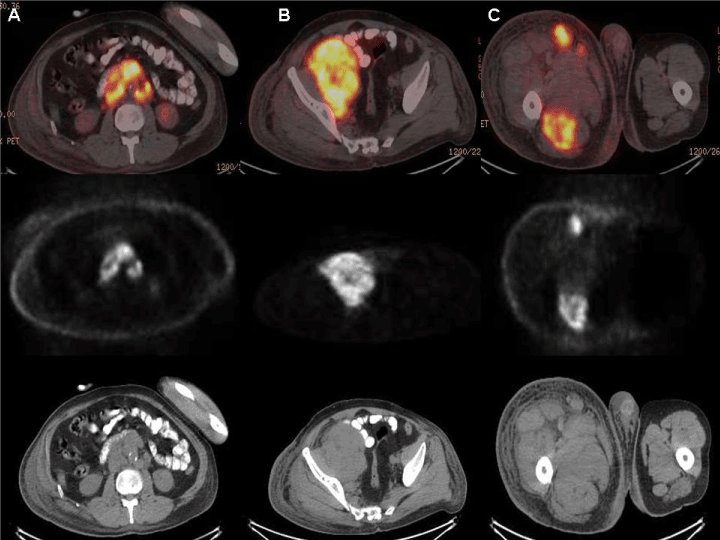

Figure 2. Bilateral paraaortic, aortocaval, retroperitoneal lymphadenopathies in axial PET-CT fusion, axial PET and CT images (A), right pelvic lymphadenopathies in axial PET-CT fusion, axial PET and CT (B) images and right lower extremity muscle uptake in axial PET-CT fusion, axial PET and CT (C) images. According to PET-CT imaging findings, significant increase in metabolic activity observed in muscle structures in the lower right extremity was interpreted as compatible with leukemic-lymphomatous infiltration.